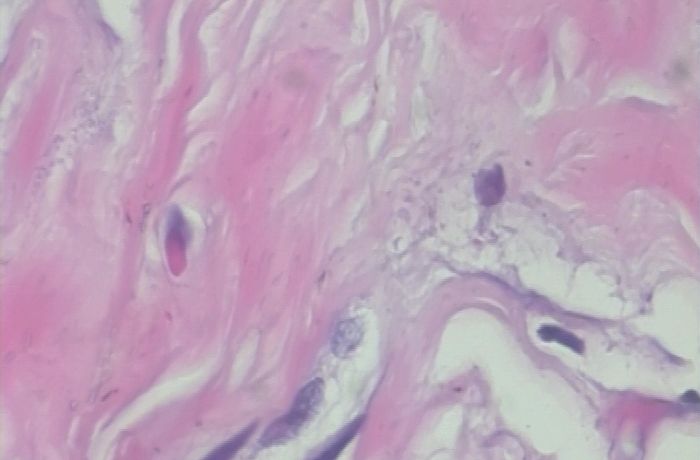

以上两张图片是良性样本